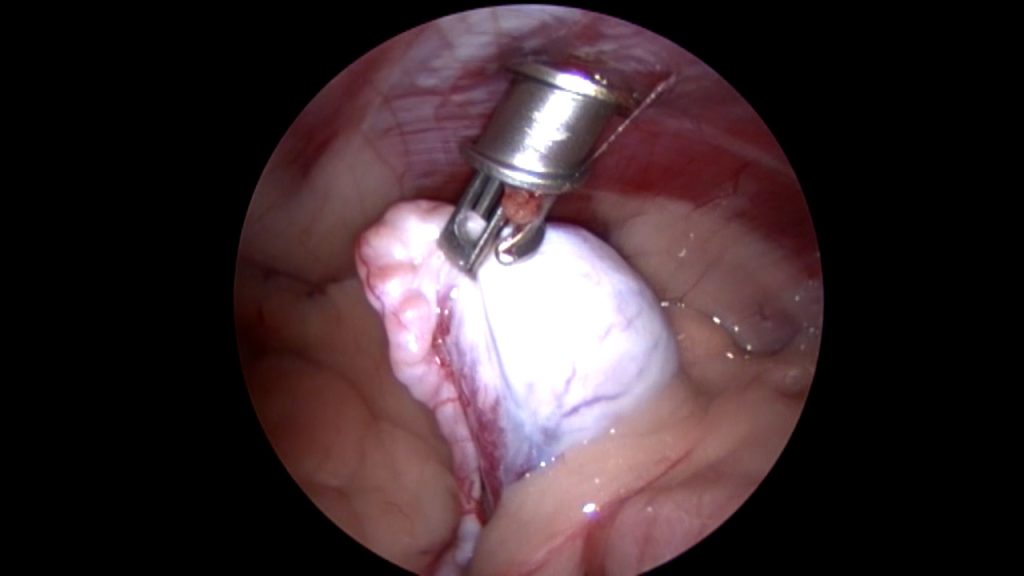

Op de operatietafel kunnen we vervolgens met behulp van de scoop de cryptorche testikel nauwkeurig lokaliseren en bepalen waar de bloedvaten zitten, die we niet willen raken. Vervolgens kan dan zeer gericht een 2e trocar (dit is een canule van bijvoorbeeld 5 mm breed, waardoor je vervolgens met een tang de buik in kunt) geplaatst worden om de testikel tegen de buikwand te halen en te kunnen verwijderen. Al met al heb je dan 2 veel kleinere gaatjes in vergelijking met een echte buikoperatie.